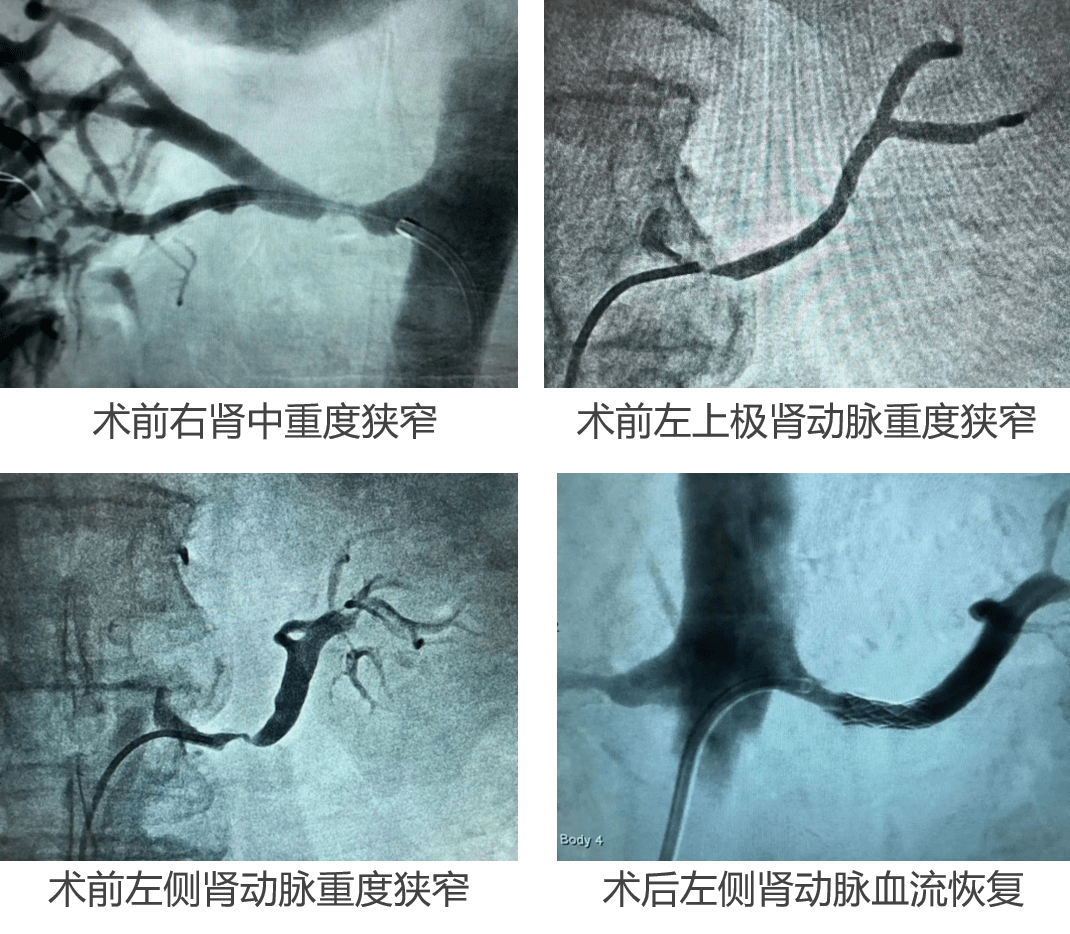

经典病例| 顽固性高血压病史30余年,肾动脉支架植入术有效缓解

经典病例 | 顽固性高血压病史30余年,肾动脉支架植入术有效缓解_手机

肾动脉支架植入术前